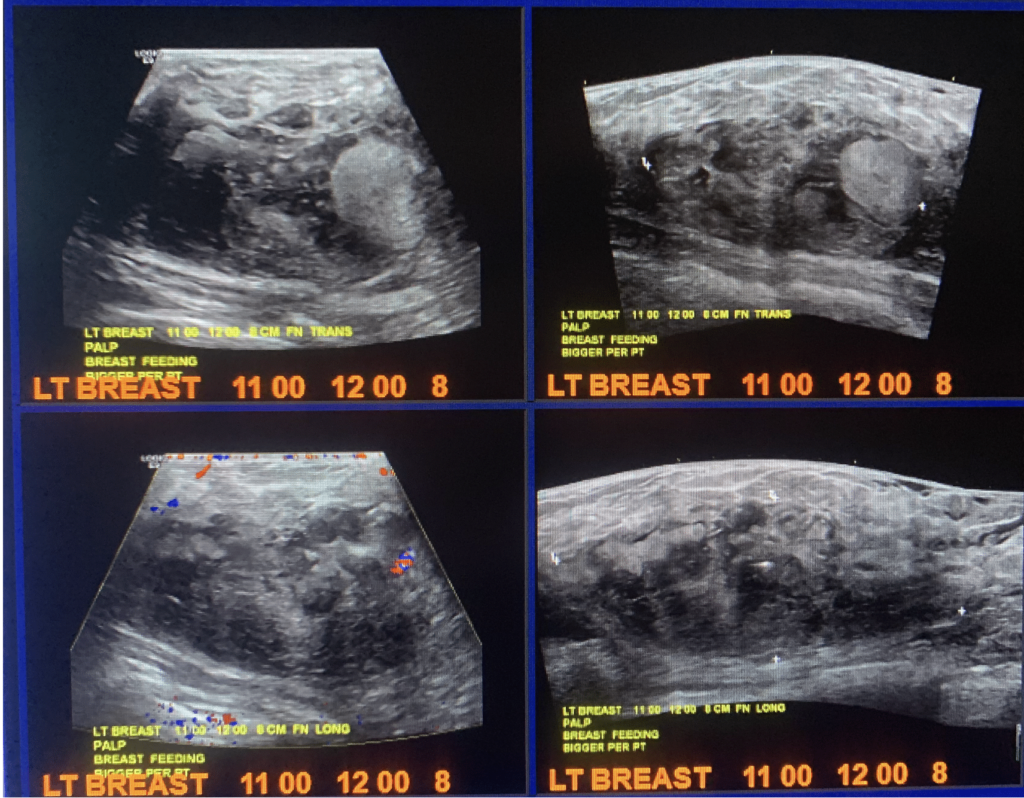

Lactating Adenoma

Lactating adenomas are benign (non-cancerous) masses comprised of dense glandular tissue and most commonly occur in the upper outer part of the breast. They can present during pregnancy or lactation and likely are related to hormonal stimulation. They may become large; however, they reduce in size as a woman progresses further in the postpartum period and eventually disappear when lactation is complete. They can appear similar to fibroadenoma on breast imaging, as smooth, oval lesions. Diagnosis can be confirmed with a core needle biopsy, but they do not require surgical excision.